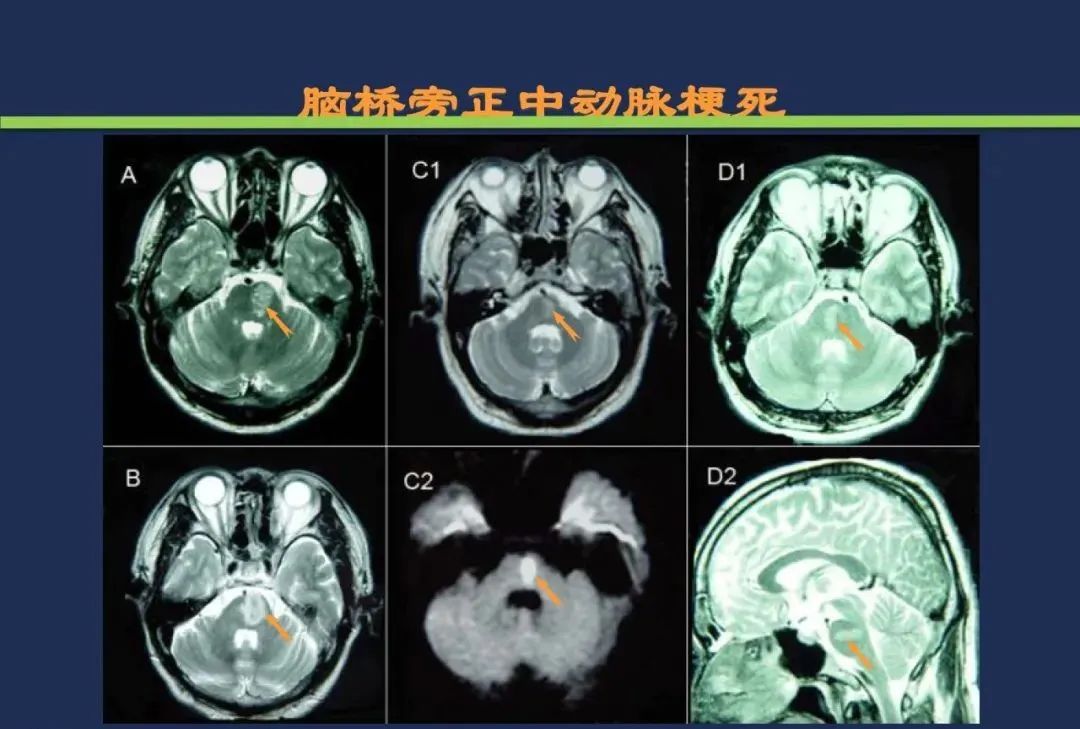

脑桥旁正中动脉